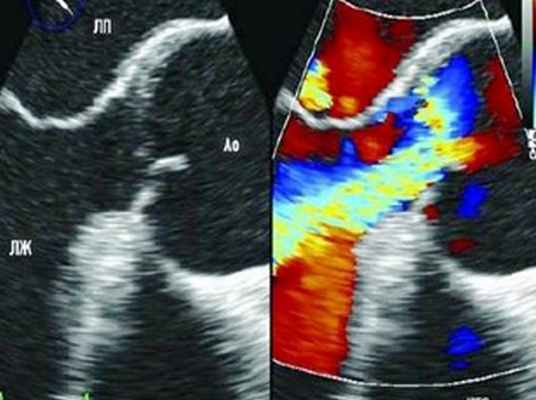

Под местной анестезией 10%-ным раствором лидокаина после внутривенного введения 2 мл раствора реланиума выполнена ЧП ЭхоКГ. Створки аортального клапана оказались неизмененными, аорта в области клапана не расширена, диаметр ее здесь равен 3.5 см. В 2 см от места прикрепления створок аортального клапана визуализируется отслоившаяся интима (рис. 2) с формированием ложной аневризмы в области задней стенки. Диаметр аорты в этой области составляет 6.2 см. При цветовом допплеровском картировании в нижней части отслоившейся интимы обнаружено отверстие размером 2.4 см (рис. 3) Отслойка интимы распространяется до дистального отдела дуги аорты, диаметр которой не превышает 3.5 см. Нисходящий отдел аорты не изменен и не расширен (2.6 см).

Рис. 2. Чреспищеводная ЭхоКГ. Двухмерное изображение аорты по длинной оси. Стрелками показана отслоившаяся интима.

Fig. 2. Transesophageal echocardiography: two-dimensional image of the aorta along the long axis. Arrows point at the detached intima.

Рис. 3. Чреспищеводная ЭхоКГ. Двухмерное изображение аорты по длинной оси. Цветовое допплеровское картирование. Видно (желтый цвет) движение крови по каналу, образованному отслоившейся интимой.

Fig. 3. Transesophageal echocardiography: two-dimensional image of the aorta along the long axis. Color Doppler. Yellow is a blood flow along the channel formed by the detached intima.

Помимо гипертрофии миокарда левого желудочка, склеротически измененных створок аортального клапана и наличия его недостаточности I степени, обращало на себя внимание расширение восходящего отдела аорты до 4,5-5,1 см (на различных уровнях) (рис. 1). Исследование средних отделов восходящей аорты (рис. 2) позволяло выявить нитевидную, невыраженно флотирующую структуру, расположенную по передней стенке аорты, формирующую истинный и ложный каналы аорты, которые более детально верифицировались в режиме ЦДК (рис. 3). В слепом участке ложного канала определялись тромботические массы. При исследовании из супрастернального доступа в области дистального отдела восходящей аорты и ее дуги лоцировался участок отслоения интимы (рис. 4). В остальных отделах аорты, доступных для визуализации, патологии выявлено не было. Таким образом, ультразвуковое исследование сердца позволило диагностировать расслаивающую аневризму восходящего отдела и дуги аорты (тип II по De Bakey). Проведенная МСКТ подтвердила данный диагноз (рис. 5).

Рис. 1. Эхокардиограмма больного Ж. Режим ЦДК. Парастернальная позиция по длинной оси.

1 - аорта, 2 - левый желудочек, 3 - межжелудочковая перегородка, 4 - задняя стенка левого желудочка, 5 - левое предсердие, 6 - регургитация на аортальном клапане.

Рис. 2. Эхокардиограмма больного Ж. Парастернальная позиция по длинной оси с фокусом на восходящий отдел аорты.

1 - отслоенная интима аорты, 2 - истинный канал аорты, 3 - ложный канал аорты, 4 - тромботические массы в слепом участке ложного канала аорты.

Рис. 3. Эхокардиограмма больного Ж. Режим ЦДК. Парастернальная позиция по длинной оси с фокусом на восходящий отдел аорты. Заполнение цветом просвета истинного канала аорты.